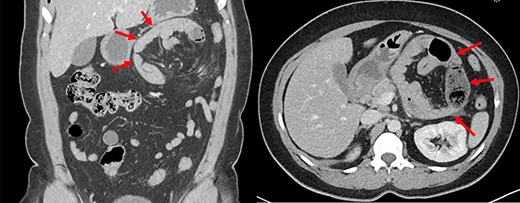

A 42-year-old female patient presented to the emergency room with acute epigastric pain, nausea and vomiting. Past medical history included hypertension and gastroesophageal reflux disease. Her past medical history did not include any prior abdominal surgery. Vital signs were normal at presentation. Abdominal examination revealed a soft abdomen with a mild epigastric tenderness. White blood cell count and lactate level were within normal limits. An abdominopelvic computed tomography (CT) scan showed a left PDH containing a jejunal loop (Fig. 1). The neck of the hernia was estimated at 4 cm. The bowel had signs of fecalization, suggesting a chronic stasis phenomenon. There was no evidence of occlusion or bowel ischemia.

Abdominopelvic CT scan depicting a left paraduodenal hernia containing a jejunal loop with fecalization (arrows).